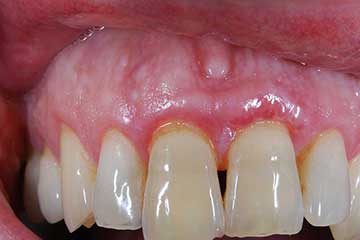

Lembo libero per correggere una recessione gengivale